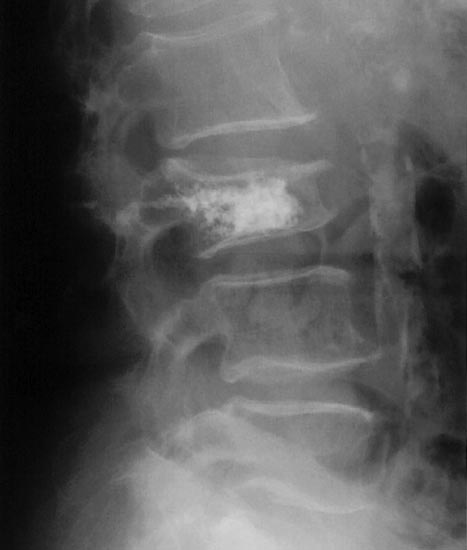

Radiological Society of North America. Osteoporosis. Available at <http://www.radiologyinfo.org/en/photocat/gallery3.cfm?image=xray-osteoporosis-vertebroplasty.jpg&pg=osteoporosis > Accessed 13 December 2014.